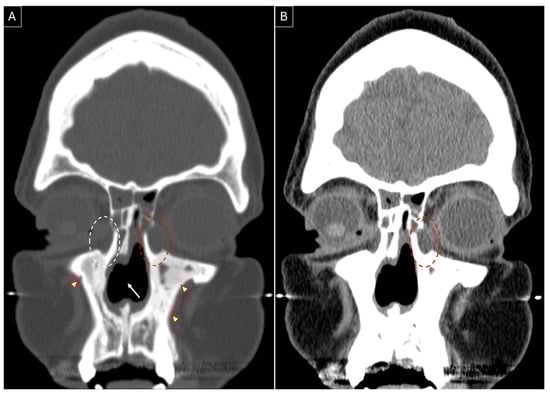

She developed complaints of right-sided epiphora in April 2023 and underwent right-sided endoscopic DCR in August 2023; Figure 3A,B highlight the sinonasal radiological findings prior to surgery. Wide marsupialization of the lacrimal sac was ensured with the placement of a Crawford stent (Figure 3C). Histopathology revealed moderate inflammation, extensive fibrosis, and squamous metaplasia. Serial debridements were performed to deal with extensive crusting at the surgical site, which settled by the seventh postoperative month, along with a complete resolution of her symptoms with low-dose methotrexate maintenance therapy.

Figure 3.

Non-contrasted sinus CT, coronal section, bone (A) and soft tissue (B) windows, showing right-sided dacryocystitis (red dotted circle). The presence of a nasal septal perforation (white arrow), osteitic bone remodelling (red arrowheads), and a previously performed right-sided hemi-modified Lothrop frontal sinusotomy can be noted (white asterisk). (C) Intraoperative endoscopic image of the right lacrimal sac medial wall (white dotted circle) after removal of the overlying lacrimal bone. The white arrow indicates tenting of the medial wall of the right lacrimal sac by the Bowman lacrimal probe.

A key observation from our review is the high success rate (100%) in endoscopic DCR over two decades (1998–2019), with no reported perioperative complications. While the sample size remains small (22 surgeries), several studies proposed methods to optimize surgical success in GPA patients, including the use of a preoperative CT for surgical planning [5,6,7,8,10], fiberoptic guidance and dye to accurately identify the lacrimal sac and distinguish the sac lumen from inflamed, thickened sac walls [8], use of silicone or Crawford tubes for lacrimal stenting to maintain postoperative patency [5,6,8,10], and high-volume postoperative saline and budesonide nasal irrigation, combined with early surgical debridement, to minimize scarring and obstruction [10]. However, none of these reports discuss patient-specific factors influencing the decision to use stenting. At our center, we routinely obtain preoperative CT scans for GPA patients undergoing endoscopic DCR, especially in cases with distorted intranasal anatomy to allow for intraoperative image guidance. It also aids in the assessment of coexisting sinus disease and the need for simultaneous sinus surgery. Our surgical protocol includes a posteriorly based mucoperiosteal flap for lacrimal bone exposure, which is then drilled to achieve complete sac exposure. A Bowman’s probe is inserted to tent the medial wall of the sac, guiding the incision (Figure 3C). Lacrimal puncta are serially dilated, followed by the use of Crawford tubes for lacrimal stenting, which are removed between 3 and 6 months postoperatively based on disease activity. Postoperative follow-up and serial endoscopic debridements are usually scheduled for the first week, sixth week, and third month. Patients are advised to perform low-pressure, high-volume saline nasal irrigations postoperatively. Given that most available data are limited to case reports and small case series (maximum sample size in reported case series = 7) [9], sharing our experience with two successful cases contributes valuable insights to the limited literature on endoscopic DCR outcomes in GPA-related epiphora.